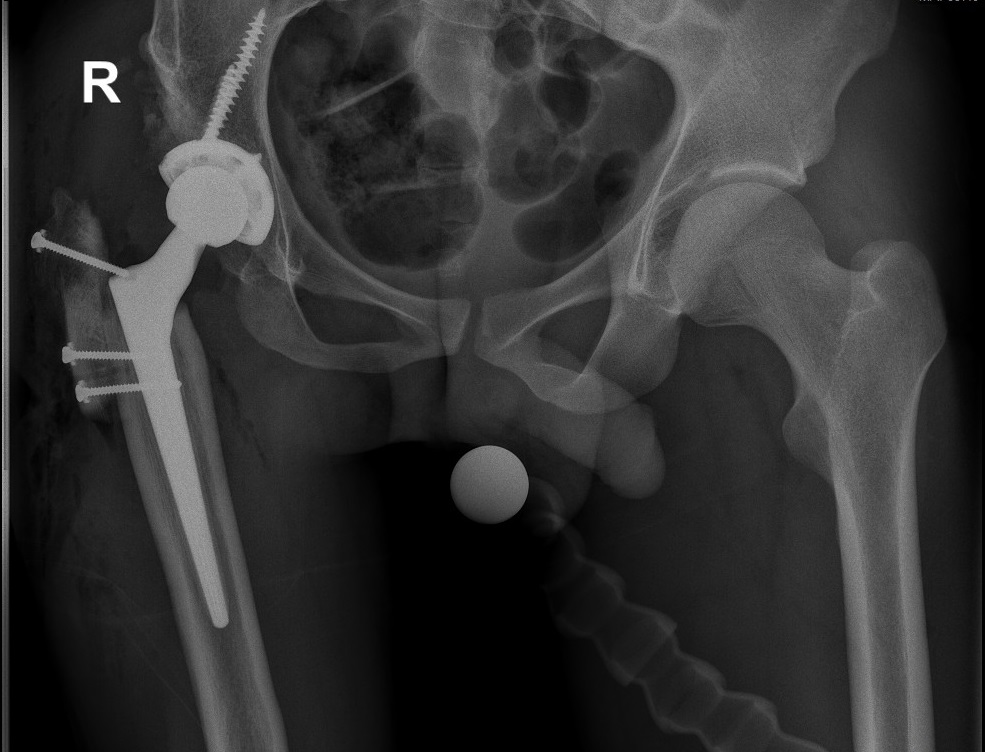

Рентгеновские снимки анкилоза суставов: Как это выглядит